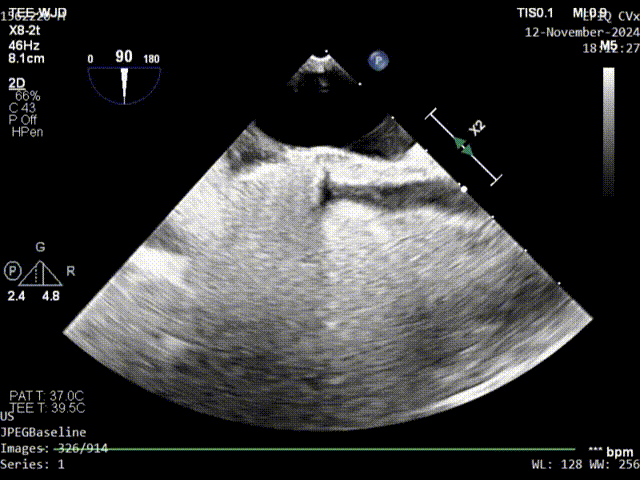

术前TEE影像

术前发泡影像